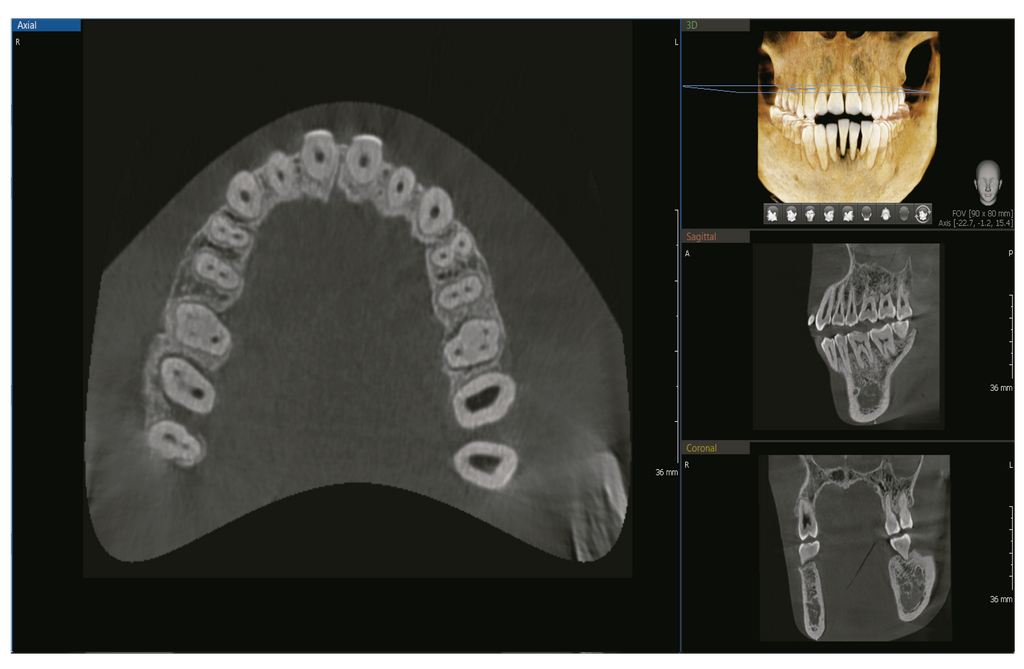

FOV INTEGRAL PARA IMÁGENES 3D

Con un FOV 8×8, las imágenes permiten realizar diagnósticos fundamentales y planificar el tratamiento, incluyendo las áreas maxilar y mandibular, en una sola exploración.

Es útil para cirugías de implantes complejas y diagnósticos de ATM izquierda/derecha.